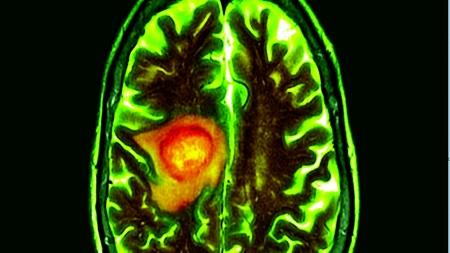

خبرني - قال باحثون صينيون إنهم أحدثوا اختراقاً في مجال تكنولوجيا واجهة الدماغ والحاسوب، بعدما أجروا أول عملية على مستوى العالم لزراعة حاسوب في كائن غير بشري.

وذكرت وسائل إعلام رسمية في الصين أن علماء صينيين أجروا أول عملية تدخلية، في إطار ما يعرف بتكنولوجيا واجهة الدماغ والحاسوب «بي سي أي».

وتحدث هذه التجربة قفزة كبيرة إلى الأمام في علوم الدماغ وفقاً لما ذكر موقع جامعة نانكاي الصينية. وفي دراسة لم تخضع لمراجعة خارجية قال باحثون صينيون إنهم مكنوا قرداً من تحريك ذراع روبوتية باستخدام موجات الدماغ.